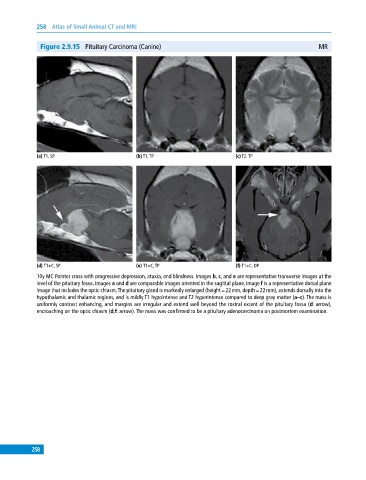

Figure 2.9.15 Pituitary Carcinoma (Canine) MR

(a) T1, SP (b) T1, TP (c) T2, TP

(d) T1+C, SP (e) T1+C, TP (f) T1+C, DP

10y MC Pointer cross with progressive depression, ataxia, and blindness. Images b, c, and e are representative transverse images at the

level of the pituitary fossa. Images a and d are comparable images oriented in the sagittal plane. Image f is a representative dorsal plane

image that includes the optic chiasm. The pituitary gland is markedly enlarged (height = 22 mm, depth = 22 mm), extends dorsally into the

hypothalamic and thalamic regions, and is mildly T1 hypointense and T2 hyperintense compared to deep gray matter (a–c). The mass is

uniformly contrast enhancing, and margins are irregular and extend well beyond the rostral extent of the pituitary fossa (d: arrow),

encroaching on the optic chiasm (d,f: arrow). The mass was confirmed to be a pituitary adenocarcinoma on postmortem examination.